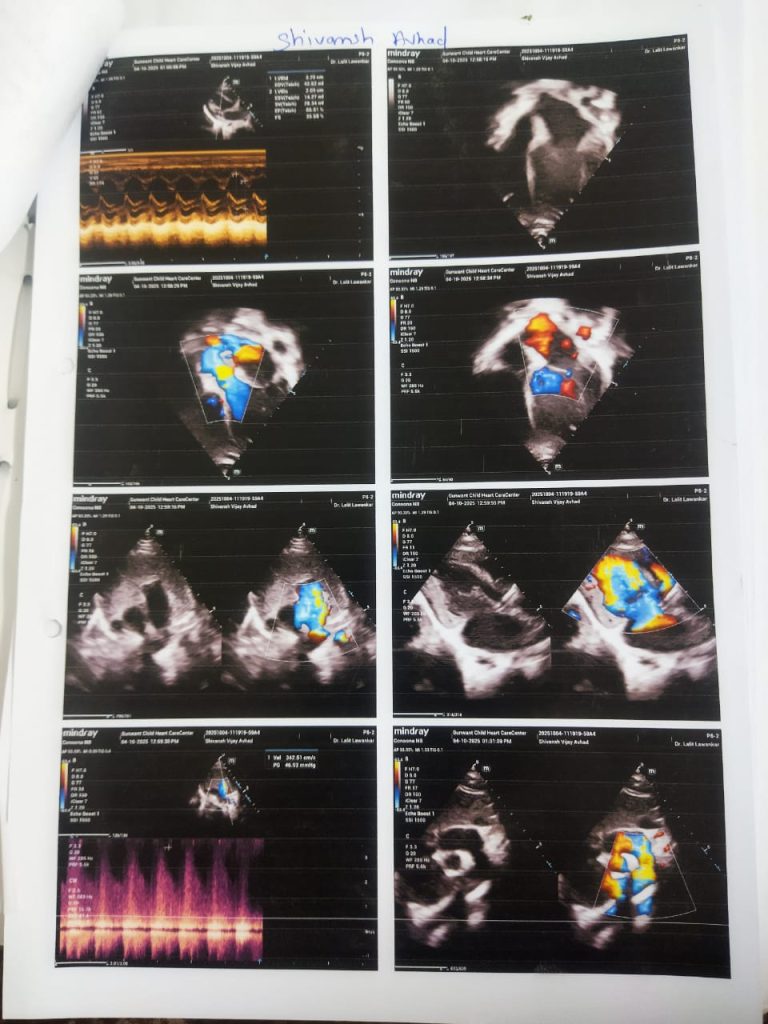

This is to certify that Master. Shivansh Palak Vijay Avhad is 6 months old child suffering from Large Patent Arteriosus , Dilated LA,Lv, Moderate Pah.